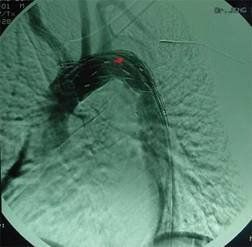

所謂手術指征,也就是手術適應症,是指當某種疾病符合診療常規所規定的標準,採用非手術治療方式無法治癒疾病,採用手術方式將有助於疾病的治療時,所應採用的手術方式。任何一項應予手術的疾病都有一定的標準,比如剖腹產的手術指征適用於孕婦不能經陰道分娩,或陰道分娩危及孕婦或胎兒的安全時;腰椎管狹窄症手術指征是:活動後腰及腿痛,影響生活工作,經保守治療不愈者,進行性跛行加重,或站立時間漸縮短者。等等。 患者具備手術指征,但醫師拒絕手術或實施了錯誤的手術,醫師就要承擔相應的責任。如第一篇案例二“乾某訴某市三級醫院主動脈瘤延誤手術案”就是此種情況。